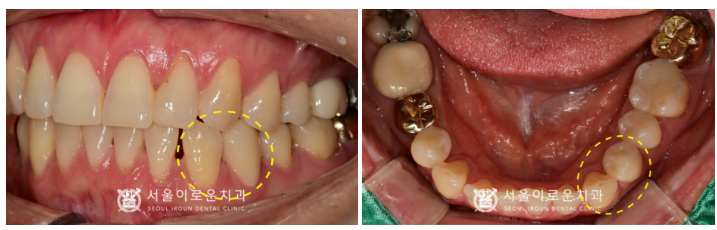

그리고 불편감을 호소하신

오른쪽 위턱 어금니 외에도

왼쪽 아래턱 송곳니(#33)와

바로 뒤 첫 번째 작은 어금니(#34)는

치아 사이 부분에서 충치가 관찰되었는데요.

충치의 범위와 진행 정도,

치아 검사를 통해

송곳니(#33)은 레진 치료,

첫 번째 작은 어금니(#34)는

신경치료 후 크라운 수복을

진행하기로 하였습니다.

더불어 오른쪽 임플란트 수술 후

픽스쳐가 잇몸뼈에

단단히 고정되기를 기다리는 동안

왼쪽 아래턱 치아 치료를 진행하였는데요.

송곳니(#33) 충치 제거 후 레진을

신경치료 후 크라운까지

깔끔하게 마무리해 드렸답니다.